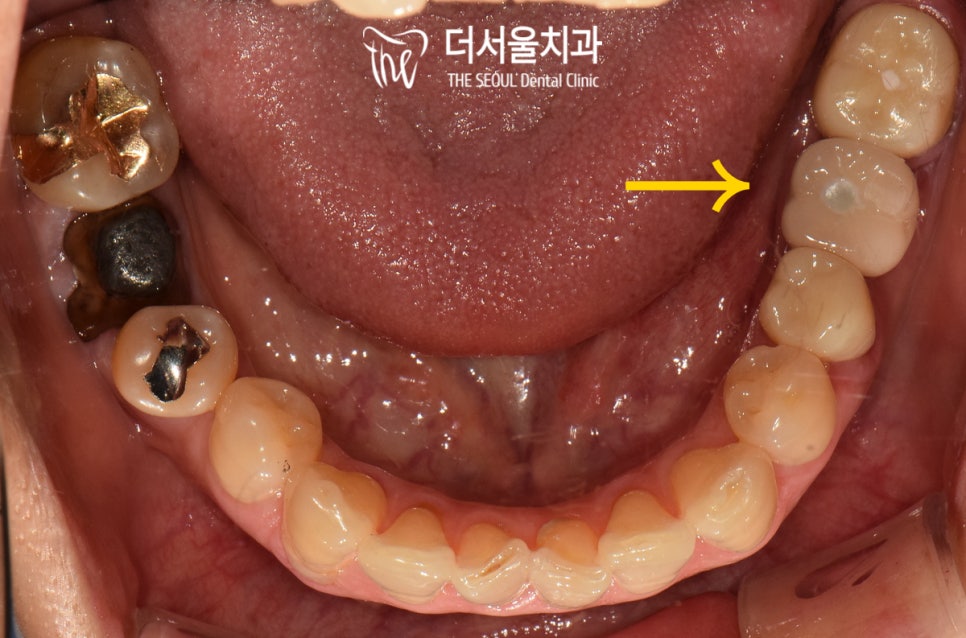

실제로 기존 보철을 벗겨본 결과..

심하게 썩어있는 지대치를 확인할 수 있었습니다.

이 정도라면 통증도 심하고

동요도 느껴졌을 정도인데요.

치관 대부분이 손상되어

구강 내에 남아있던 어금니 한 곳이

결국에는 빠져버리게 된 것입니다.